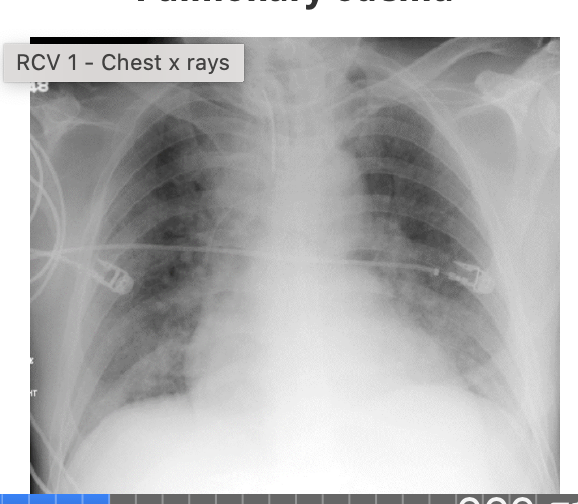

-check the ratio of the heart size: width of thorax (normal adult ratio is less than 50%)

-if heart is enlarged, it may indicate cardiomegaly, but you cannot judge this accurately on AP film

-check borders - edges of the heart should be clear which ensures nothing is obscuring this silhouette eg pulmonary oedema

what is an example of a condition in which the heart borders are blurred?

A

-pulmonary oedema